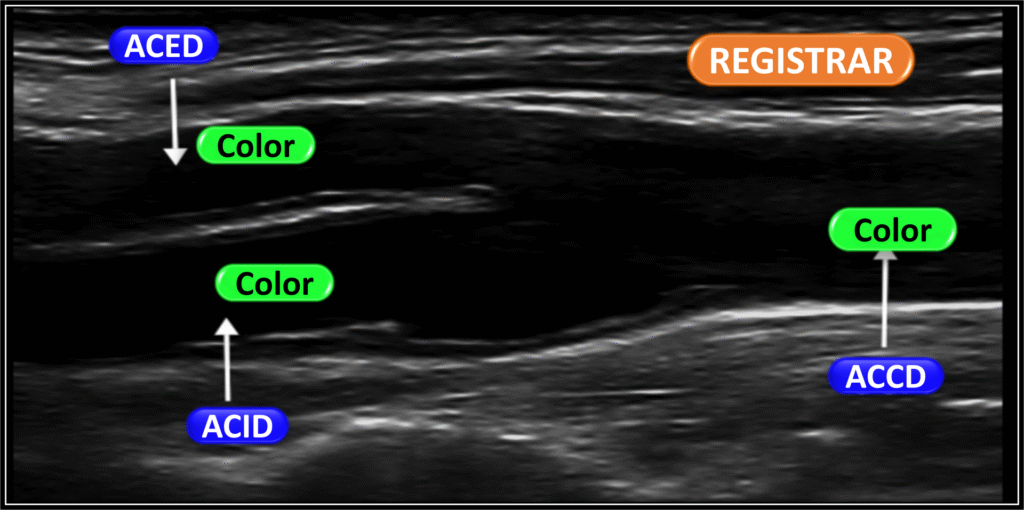

Imagens para registrar

O Doppler de carótidas é uma ferramenta fundamental para avaliar doenças arteriais.

Além da observação dinâmica em tempo real, é essencial registrar imagens que contenham as informações mínimas necessárias para um diagnóstico preciso.

Essas imagens devem incluir cortes longitudinais e transversais das artérias carótidas comuns, internas e externas. É importante destacar áreas de interesse, como placas, estenoses ou tortuosidades (kinks).

Também é indispensável registrar o Doppler colorido espectral com os valores das velocidades sistólicas e diastólicas — especialmente nas regiões com turbulência ou fluxo alterado.

Esses registros fotográficos permitem uma revisão diagnóstica mais segura e servem como base para comparações futuras, garantindo um acompanhamento detalhado e confiável da evolução das condições observadas.